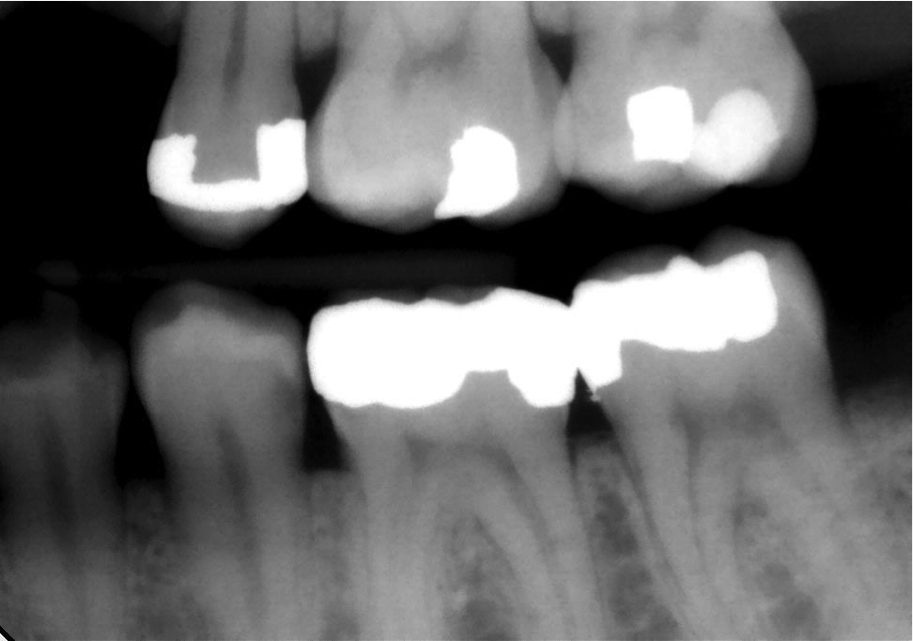

However, in the past decade, a new generation of low-shrinkage composites was developed specifically for bulk placement. These products’ advantages for placement relative to composites designed to be layered are radiographically apparent (Figure 1 and Figure 2); areas of porosity raise concerns about recurrent decay, and with a highly viscous composite, the chance of trapping air bubbles is significantly increased, compared to a dense, homogeneous void-free composite resin (Figure 2).2

Fig 1. Problems with incremental composite placement include potential voids and porosity when layering.

Figure 1

Fig 2. Radiograph shows single 4-mm incremental bulk-fill placement compared to using a layered method.

Figure 2